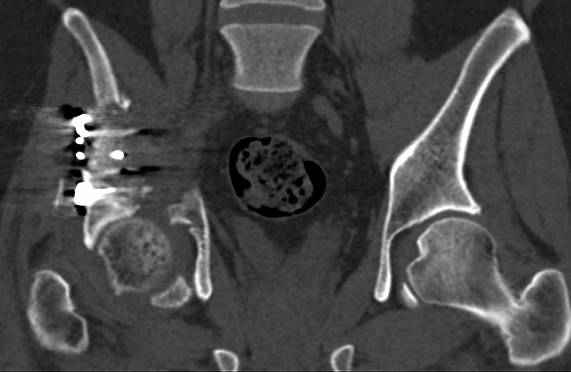

высылаю дополнительно сканы.

итак, второй вариант: высокий двухколонный с вовлечением КПС... Ни одно из основных повреждений не репонировано, кроме задней стенки. Скорее всего попытка реконструкции вертлуги сейчас будет очень травматичной и не очень эфективной, т.е. вероятный риск более значим, чем ожидаемая польза... Лучше подождать, и потом сразу эндопротез

>Вопрос к знатокам: Так что это?

к таковым себя не причисляю, но...обычное дело для нашей страны - выкладывать 3D и не показывать стандартные проекции Judet. Дигност представляет те ракурсы, которые по-его мнению наиболее информативны, более того комп сам достраивает какие-то мелкие повреждения по 3D по своему усмотрению. По данной реконструкции можно предполагать высокий двухколонный перелом с оскольчатыми передней и задней колоннами, оскольчатую высокую переднюю колонну с задним полупоперечником или одно из перечисленных с вовлечение КПС. У меня впечатление за второй вариант, но нужно обследовать нормально - проекции, сканы.